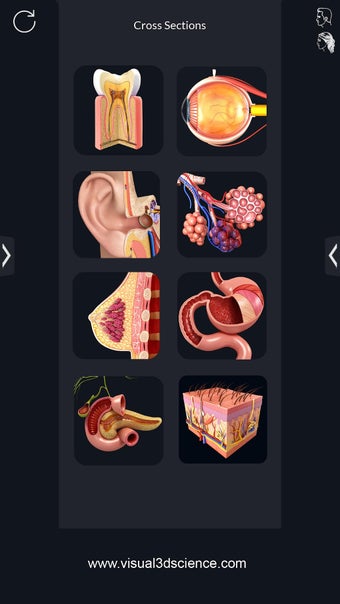

¿Qué ofrece la aplicación?

Puedes seleccionar cada parte del cuerpo por separado para ver su nombre o leer información relacionada. Puedes ocultar y mostrar cada parte del cuerpo, así como rotar 360° alrededor de un modelo 3D altamente realista. Puedes dibujar en la pantalla o compartir capturas de pantalla con tus amigos. Puedes encontrar la definición de cada parte del cuerpo y su anatomía.